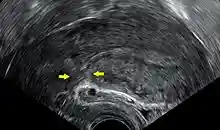

![]()

Transvaginal ultrasonography of a uterus years after a caesarean section, showing the characteristic scar formation in its anterior part